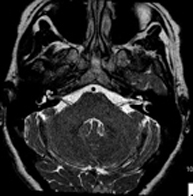

- Neuroradiology

- Brain MRI (cranial)

This non-invasive diagnostic procedure uses an electromagnetic field and radio waves (from a transmitter and receiver) to acquire high-definition anatomical images of the brain. It is a radiation-free procedure. Indicated for: vascular problems, memory loss, epilepsy, headache, malformations, suspected tumour, meningitis.

- Brain MRI spectroscopy

This non-invasive diagnostic procedure uses an electromagnetic field and radio waves (from a transmitter and receiver) to acquire high-definition anatomical images of the brain. It is a radiation-free procedure. This is followed by a qualitative and quantitative measurement of various metabolites (substances) to help characterise lesions. Indicated for: tumours, metabolic disorders, infections, epilepsy.